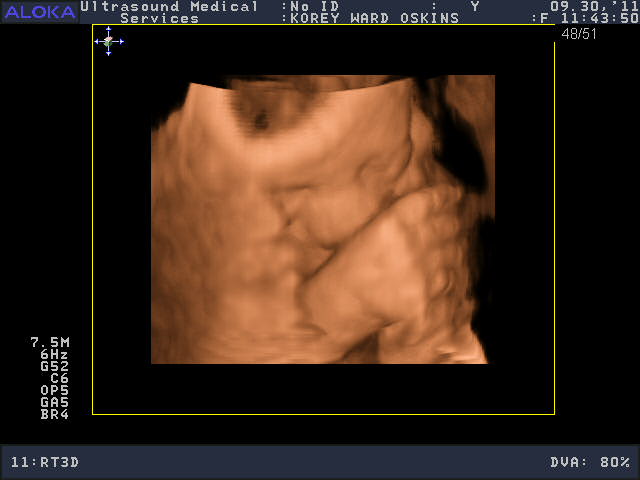

He was a very stubborn baby, so it was really kind of nerve-wracking at first thinking we might not get a single good picture. His face was squished up against the placenta and he wouldn’t budge. You’ll see that in the pictures below; it looks like an enveloping cloud or a scallop shell. Finally he moved a bit and we got some glimpses of his face. We saw him make some facial expressions, wiggle his fingers, and move his mouth around. We were curious to see whose nose he would have, and in some pictures, it looks like he has Josh’s, in others, mine.

So who do you think he looks like?

He is sooooo cute! Personally, I think he looks like ME.